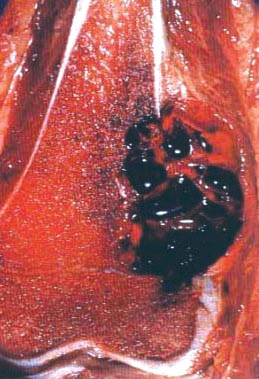

- Conventional (high grade intramedullary) osteosarcoma:

- Intramedullary mass: usually a metaphyseal epicenter with cortical permeation and a soft tissue component that raises the periosteum

- Size (mean): 5 - 10 cm

- Cut surface: gritty and mineralized (hard); may have cartilaginous areas (chondroblastic osteosarcoma), hemorrhage, necrosis and cystic change

- Telangiectatic osteosarcoma: the tumor is multiloculated with large blood filled spaces; high grade malignant cells and neoplastic bone in septa (the imaging differential diagnosis is with aneurysmal bone cyst)